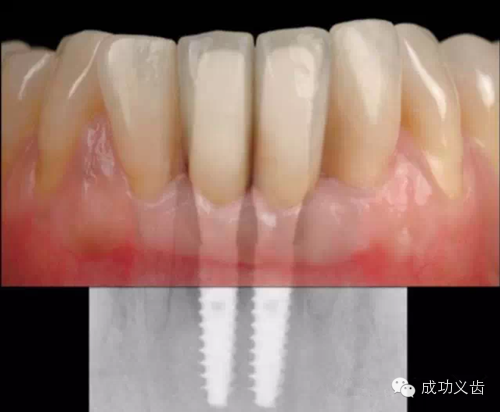

图2.延期种植2,2014年不论是从照片还是X线上,都显示出种植周围软硬组织稳定,颜色粉嫩!

图4.即刻种植2,2013年复查。种植体周围骨组织稳定,龈乳头依然尖锐。颜色粉嫩,赏心悦目。